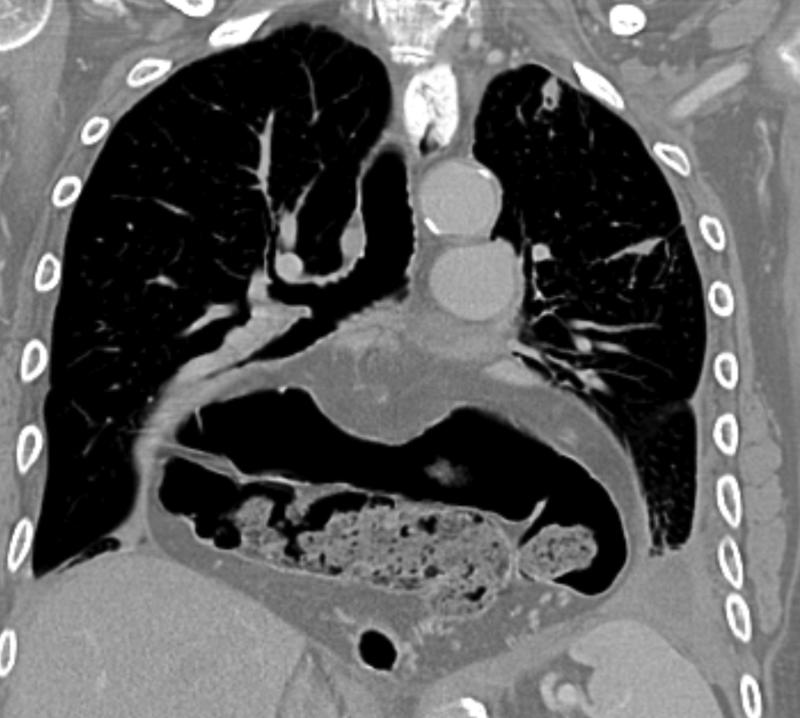

Mediastinum

Hiatus Hernia

Hiatus hernia containing stomach and transverse colon

Hiatus hernia containing

stomach and transverse colon